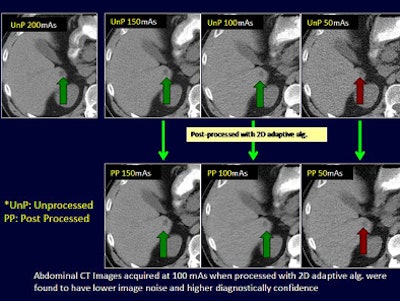

- Abdomen mAs settings: 200, 150, 100, 50

Regardless of radiation dose, postprocessing with image filters improved subjective noise for both chest and abdominal CT and helped lower CT radiation dose levels for the chest by up to 40 mAs and for the abdominal CT by up to 100 mAs, Singh said.

The quantitative average image noise in postprocessed low-dose chest and abdominal CT images was significantly lower than in low-dose unprocessed images (p < 0.001).

Although the diagnostic confidence of low-dose postprocessed images was high at 40 mAs for chest CT, postprocessed abdominal CT images were rated as "fully confident" only at 100 mAs and not 50 mAs, the group reported.

Adaptive filtering decreases image noise and enhances the diagnostic confidence of low-dose chest (40 mAs) and abdominal (100 mAs) CT exams, they concluded.